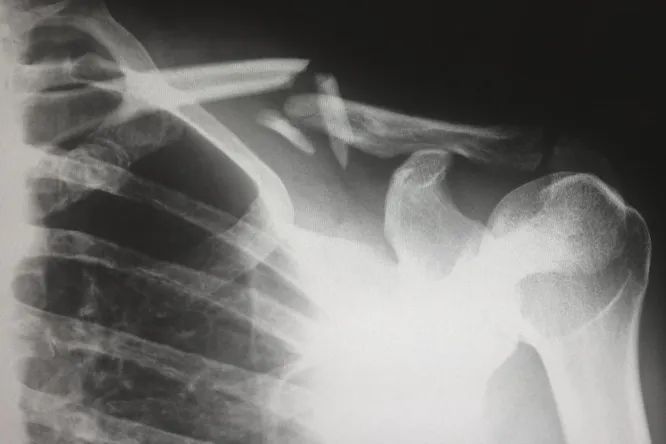

Ультратонкие и гибкие электронные устройства можно имплантировать в поврежденные кости, чтобы следить за их состоянием и подбирать оптимальные варианты лечения

Проблемные травмы костей, вызванные различными заболеваниями, например, остеопорозом, вынуждают пациентов проводить в больницах очень много времени. При этом больным могут назначать препараты для ускорения заживления костей или улучшения плотности костной ткани, но эти лекарства могут иметь побочные эффекты. Поэтому врачам необходимо более точно оценивать степень повреждения, чтобы подбирать дозировки.

В этой ситуации ученые из Аризонского университета (США) предложили новую технологию — электронику, которая может собирать информацию о состоянии костной ткани, а также об общем здоровье организма. Новшество заключается в том, что она встраивается непосредственно в поврежденную кость, а не «приклеивается» сверху. Верхние слои костной ткани обновляются точно так же, как и наружный слой кожи — эпидермис, поэтому если прикреплять устройство с помощью традиционного медицинского клея, то оно отвалится через несколько месяцев. Чтобы решить эту проблему, один из авторов исследования, профессор ортопедии и биомедицинской инженерии Джон Сивек предложил концепцию особого клея, который содержит частицы кальция с атомной структурой, подобной клеткам костной ткани.